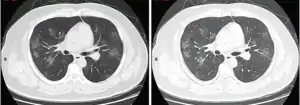

سیتی اسکن سینه روشی برای بررسی سینهپهلو است. این روش سریع و آسان است. پژوهشی نشان داده که حساسیت در تشخیص کووید-۱۹، ۹۸ درصد است در حالی که حساسیت در تشخیص با کمک PCR، برابر با ۷۱ درصد است.[9][1] البته پژوهش مستقلی برای میزان موفقیت این روش در تشخیص میان کووید-۱۹ با دیگر عفونتهای ویروسی ارائه نشدهاست.

یافتههای سی تی اسکن

تصویری از تغییرات پیشرونده در سی تی اسکن